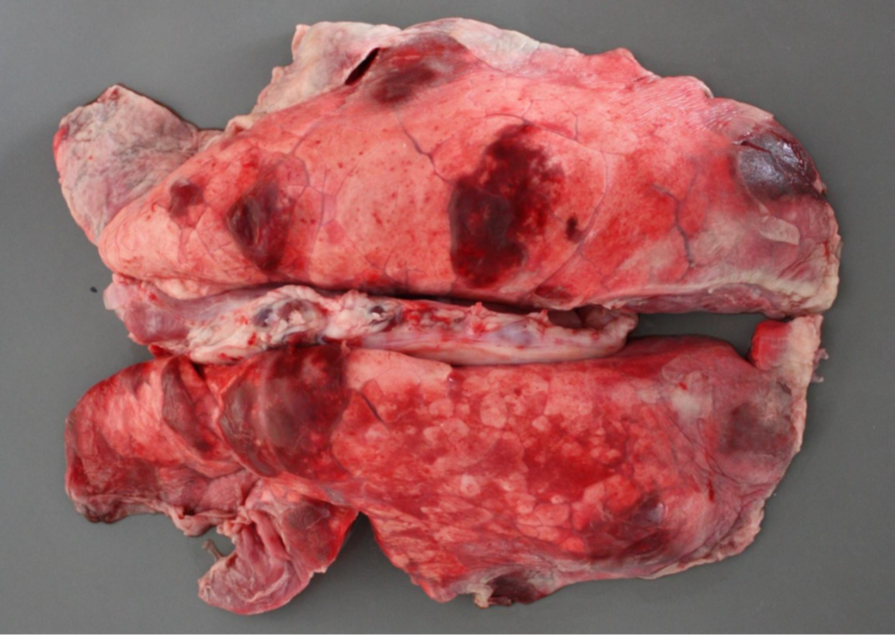

Schwein, Lunge: hochgradige, akute bis subakute, multifokale, fibrinöse Pleuropneumonie

- zufällige Verteilung der der Parenchym- und Pleuraveränderungen:

- in Spitzen- und Hauptlappen finden sich multiple landkartenähnliche Herde von roter bis dunkelroter Farbe und verfestigter Konsistenz

- multifokale, gelblichgraue Beläge auf der Pleura (= Fibrin), welche überwiegend mit den Herden des Parenchyms assoziiert sind

- Interstitien teilweise verbreitert

Ätiologie

- meistens, jedoch nicht ausschließlich, bakterielle Sekundär-Erreger nach primärer Virusinfektion

Erreger-Spektrum:

- vor allem gramnegative Bakterien (HAP-Gruppe), die Erreger besitzen Endotoxin (Lipopolysaccharid) und

bilden außerdem vielfach hochpotente Exotoxine (z.B. Apx-Toxine von Actinobacillus pleuropneumoniae)

H aemophilus (Glässerella) sp.

A ctinobacillus sp. (A. pleuropneumoniae = primäre Infektion beim Sw., außerdem A. suis und A. equuli)

P asteurella sp. (Mannheimia haemolytica (Rd.), P. multocida)

- außerdem aus der Familie der Pasteurellaceae: Histophilus somni (Rd.) und Bibersteinia trehalosi (Wdk.)

- Mycoplasmen (M. mycoides subsp. mycoides Small Colony Type, der Erreger der (anzeigepflichtigen!)

Lungenseuche des Rindes) und Mycoplasma bovis

- Pilze (Schimmelpilze)

Hintergrundwissen/ Infektionsweg/ Pathogenese

- die fibrinöse Pneumonie ist eine Form der Bronchopneumonie:

- aerogene Infektion > Bronchiolitis > peribronchioläre und endobronchioläre Fortleitung:

a) peribronchiolär > entlang der interstitiellen Lymphgefäße > Thrombose der Lymphgefäße > kein

Lymphabfluß (Gewebe ertrinkt und „stirbt“ im Ödem) > auf diesem Weg wird auch die Pleura erreicht

(Pleuropneumonie)

b) endobronchiolär > Alveolen füllen sich mit Entzündungsprodukten und Zellen an (Ödem, Fibrin, PMN,

Mø)

- makroskopisch typisch ist die kranioventrale Konsolidierung des Parenchyms; eine Ausnahme stellt die porzine

Pleuropneumonie* (APP) dar, weil die kaudalen Lungenlappen oft am stärksten betroffen sind

* meistens geht die fibrinöse Pneumonie mit einer fibrinösen Pleuritis einher > fibrinöse Pleuropneumonie

- neben der fibrinösen Komponente können auch Hämorrhagien und Nekrose (Sw: helle, landkartenähnliche und

trockene Herde in der gesamten Lunge) vorkommen

- die typische bunte Marmorierung des Parenchyms des Rindes entspricht dem klassischen (protrahierten) Ablauf in

vier Stadien:

1) Anschoppung

2) rote Hepatisation (leberähnlich, hepar = Leber)

3) graue Hepatisation

4) Organisation (Karnifikation)

- Komplikationen der fibrinösen (Pleuro-)Pneumonie: Sequester (v.a. Mykoplasmeninfektionen), Pleuraadhäsionen,

Abszesse bzw. Pleuraempyeme